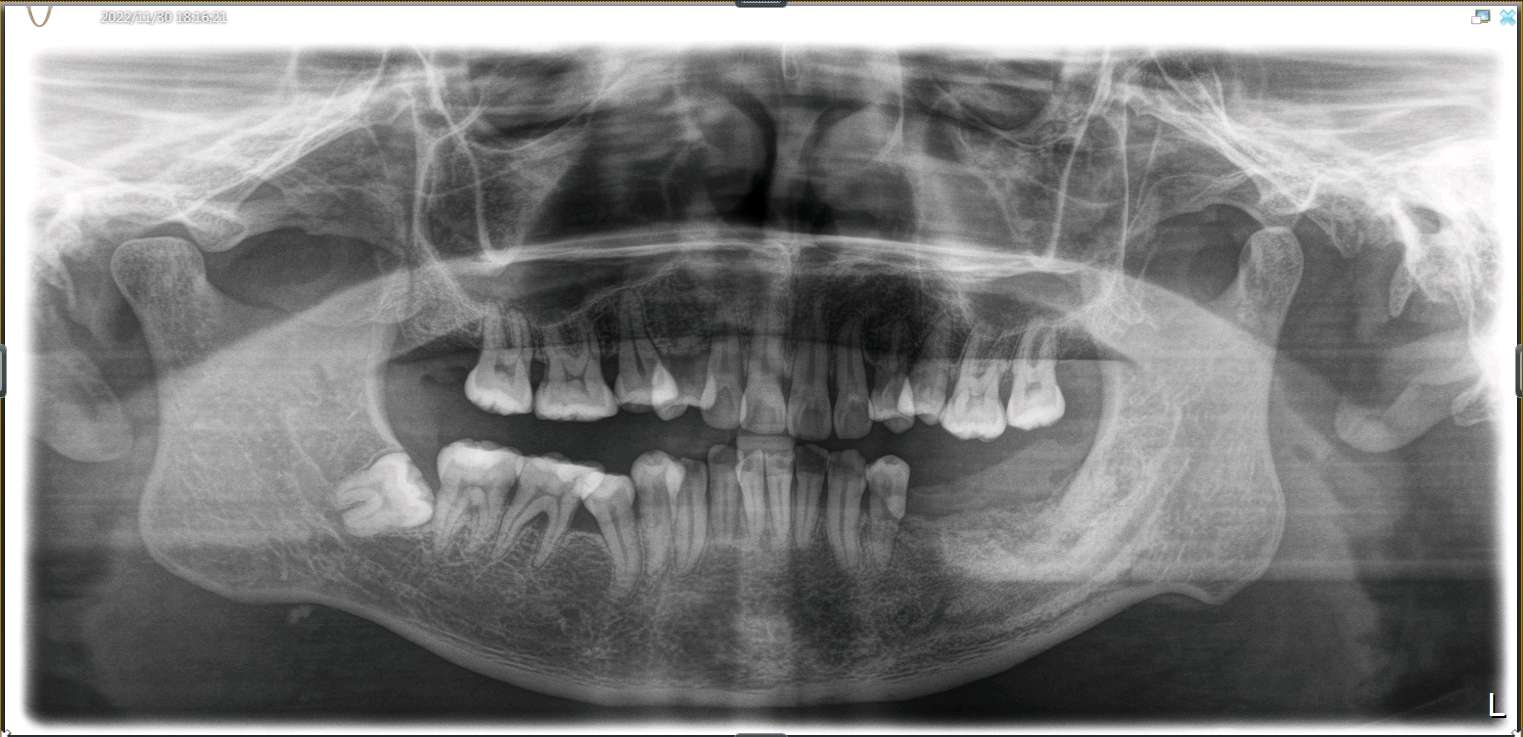

患者男,四十岁,全口口腔卫生较差。牙石+++,色素+++。左下后牙松动,X线示全口牙槽骨水平性吸收,35 36,37牙槽嵴吸收至根尖1/3。

患者自愿选择安卓健种植体。牙槽嵴吸收较多,高度和宽度不足。拔出后植入骨粉骨膜。待骨条件良好后。35植入种植体4.0*10mm;36植入种植体4.6*10mm;37植入种植体4.6*8mm。待骨结合良好后。二期三期如期进行。余近日戴牙。